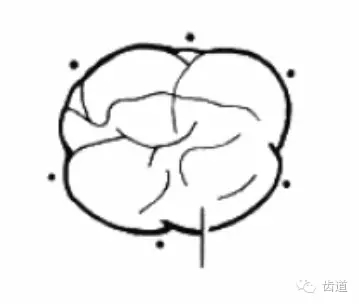

方法:下頜磨牙,頰舌側(cè)中央探查;上頜磨牙,頰側(cè)中央及腭側(cè)近遠(yuǎn)中探查

內(nèi)容:

分度:Glickman分度標(biāo)準(zhǔn)

18.webp.jpg

Furcation

19.webp.jpg

Furcation involvement

20.webp.jpg